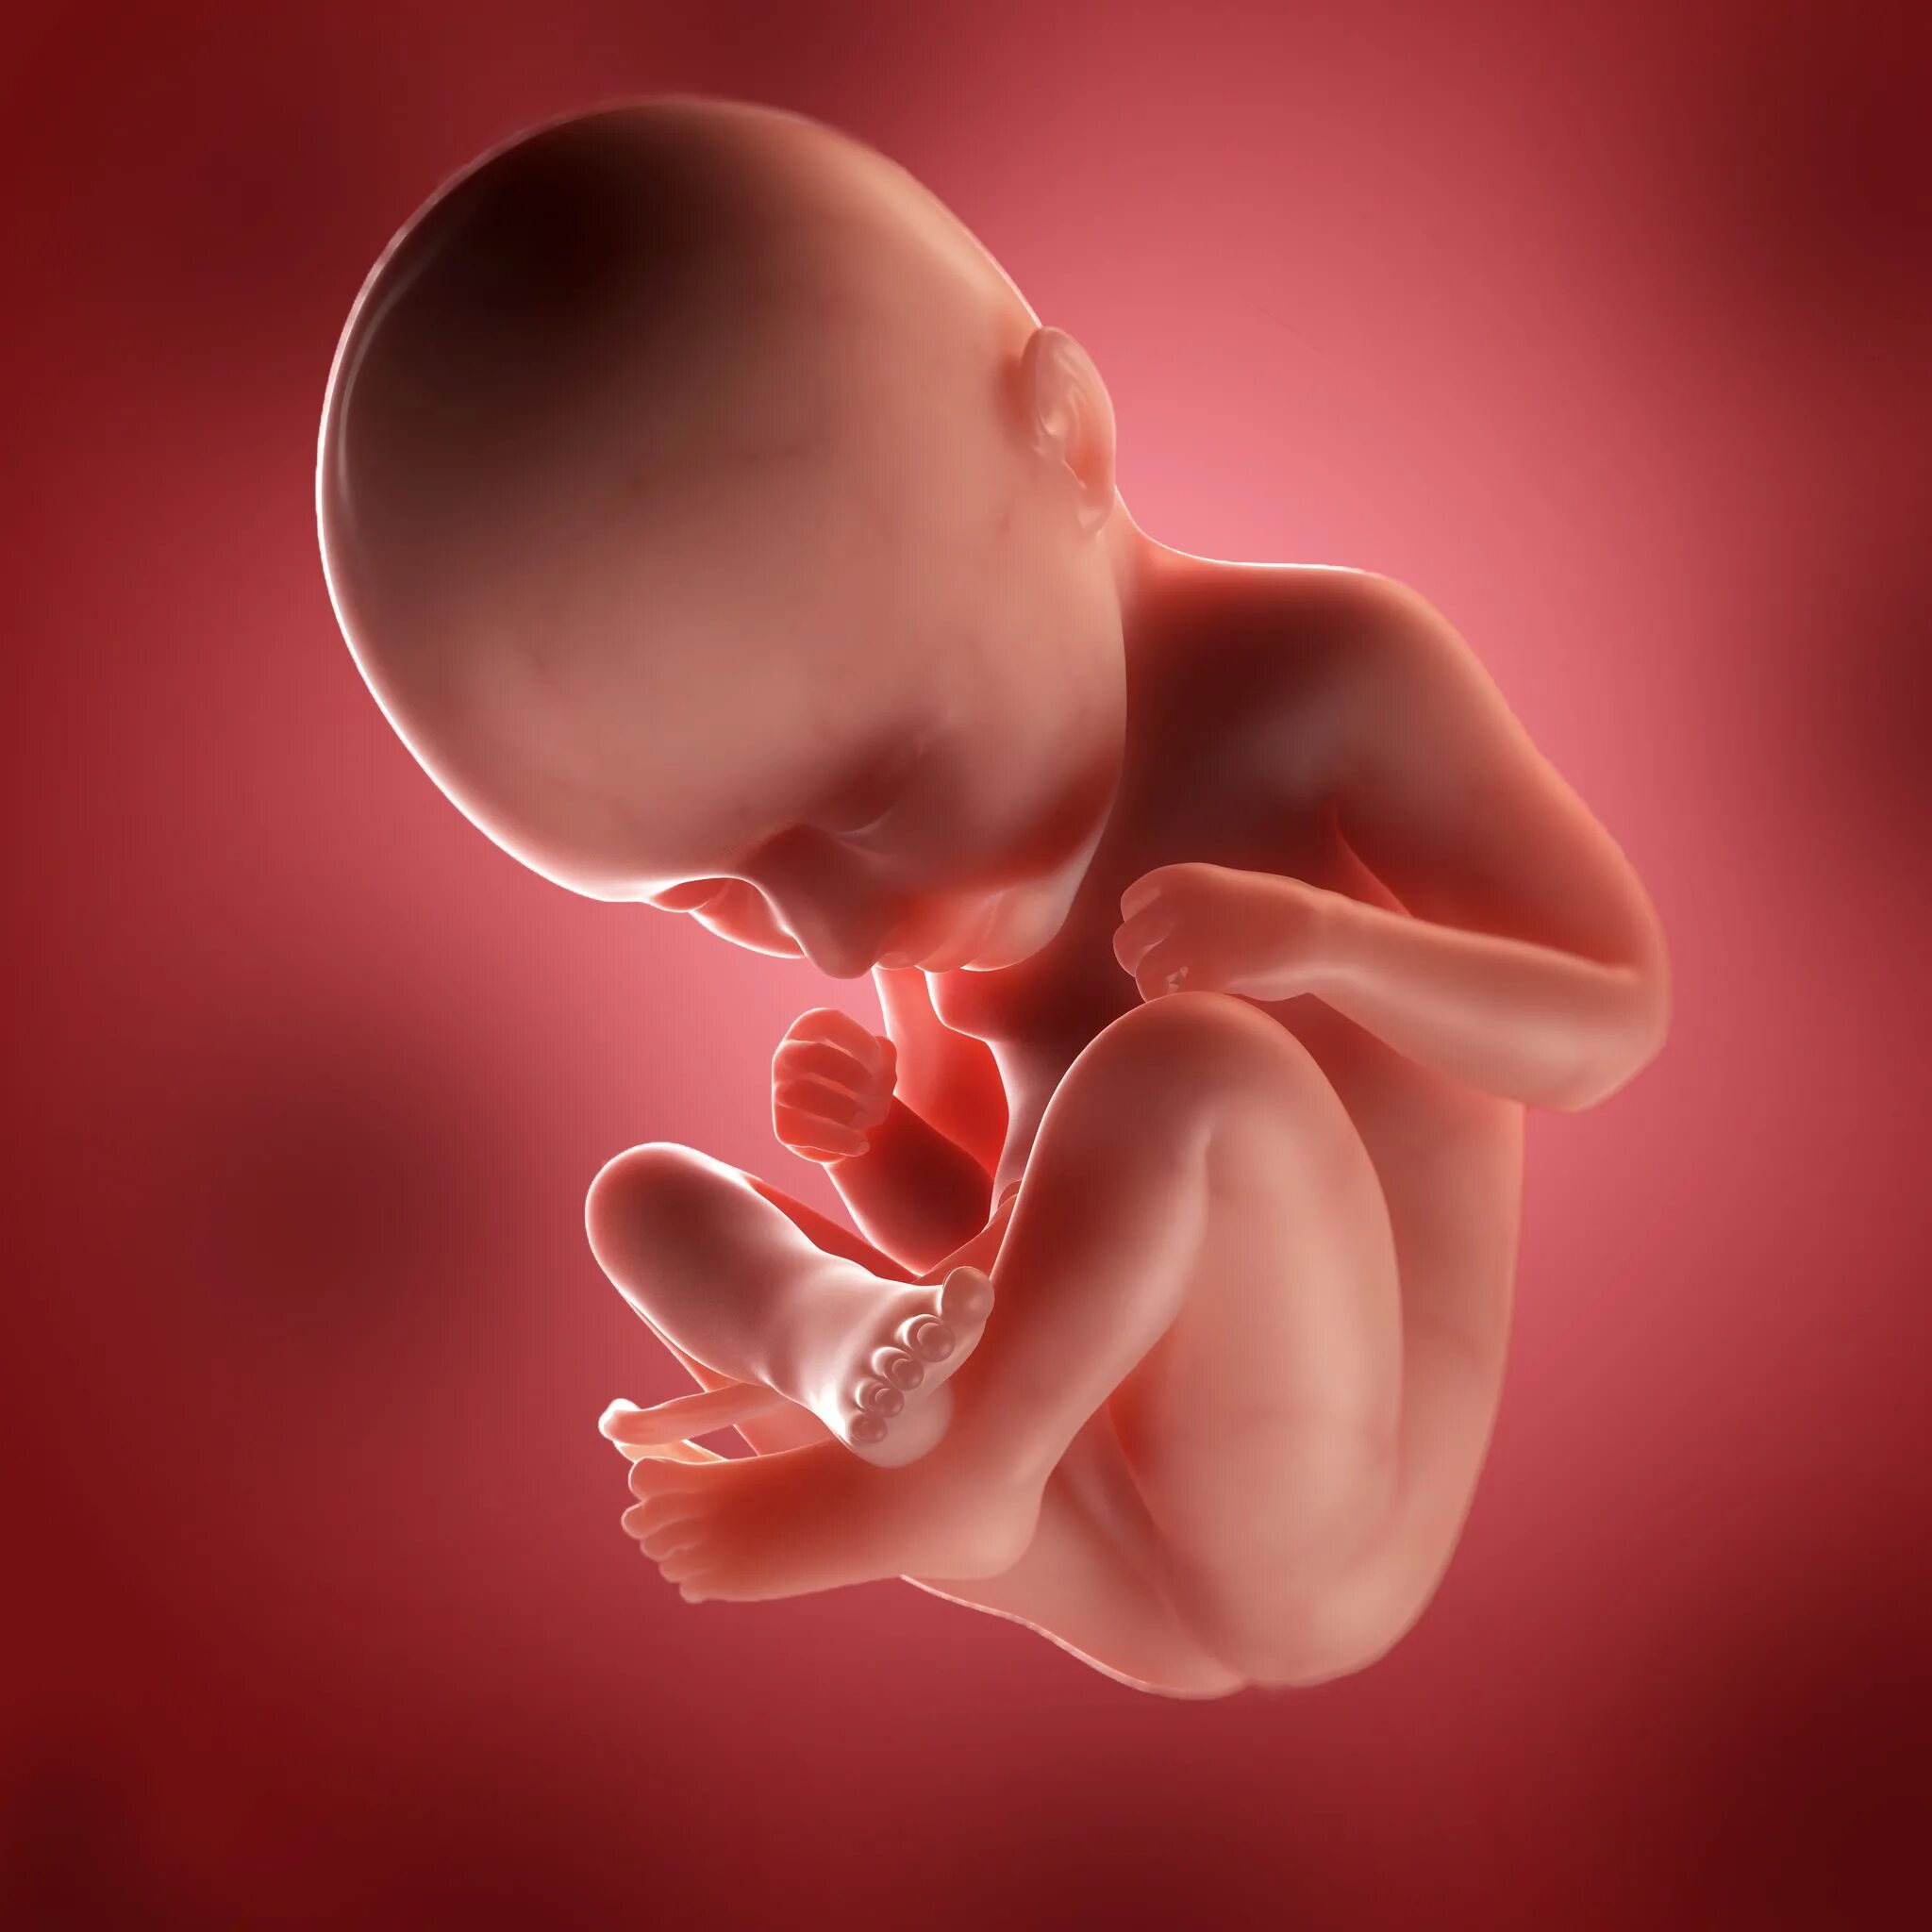

Ребенок в утробе 31 неделя